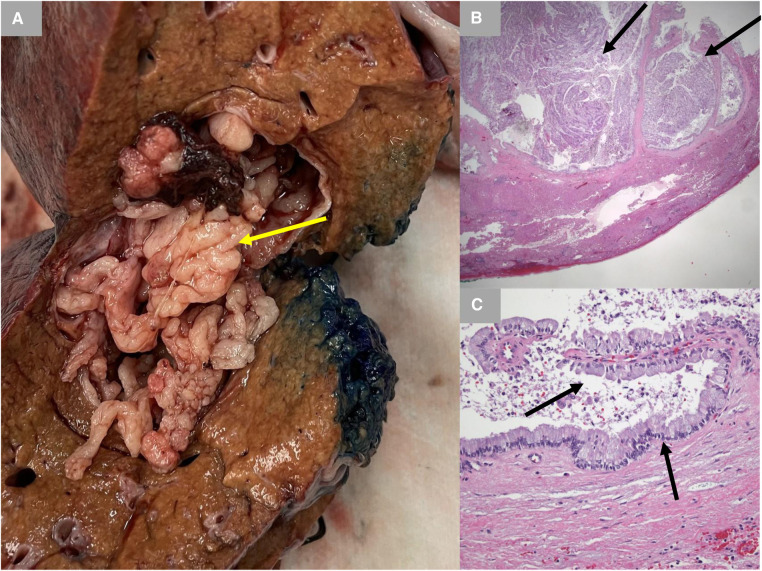

A 65-year-old male Caucasian with a history of multiple comorbid conditions presented to the emergency room with complaints of moderate constant pain at the right upper quadrant (RUQ) abdomen for the last several hours. Differential diagnoses of symptomatic cholelithiasis, cholangitis, and liver abscess were entertained. On physical examination, he was found to have normal vital signs, with icteric sclera and pain on deep palpation at the RUQ region. Upper abdominal ultrasonography (U/S) (Figure 1A) revealed a 6 cm heterogeneous mass in the left hepatic lobe and dilated gall bladder with mild sludge or stones. His laboratory results were significant for elevated liver enzymes, bilirubin and creatinine, hyperglycemia, and leukocytosis (Table 1). Subsequently, he had a hepatobiliary (HPB) iminodiacetic acid scan, which showed no excretion of hepatobiliary radionuclide related to either severe liver dysfunction or high-grade biliary obstruction. In addition, a computed tomography (CT) scan of the upper abdomen and pelvis (Figure 1B) was performed, which confirmed the U/S findings of the lesion in the left lobe of the liver and demonstrated areas of internal enhancement, and magnetic resonance cholangiopancreatography (MRCP) (Figures 1C,D) revealed mild gall bladder wall edema and a 9 mm common bile duct (CBD) dilatation of without evidence of choledocholithiasis, and it was consistent with an undetermined 5 cm mass in the left lobe of the liver. To confirm the pathology of the lesion, the referring physician performed a CT-guided biopsy, which revealed an intrahepatic papillary mucinous neoplasm. This case was discussed at the HPB multidisciplinary conference, and the patient was recommended to undergo left liver mass resection, cholecystectomy, and repair of incisional hernia. His comorbid conditions include cardiac disease, chronic obstructive pulmonary disease, diabetes mellitus, hypertension, and cerebrovascular accident. Cardiology evaluated the patient and declared him as a moderate surgical risk. He uneventfully underwent robotic left partial liver resection, cholecystectomy, lymphadenectomy, and repair of ventral hernia, and his hospital course was unremarkable. Gross pathology (Figure 2A) and histology (Figures 2B,C) revealed negative margins, and the 4.5 cm × 3.5 cm × 3.0 cm cystic structure from hepatic tissue represents the intrahepatic biliary IPMN (yellow arrow) (Figure 3) with low-grade dysplasia. The central aspect of the mass is comprised of pink-tan papillary tissue. There is no gross evidence of invasion (Figure 3). The remainder of the liver parenchyma is red-brown and firm. The patient came for regular postoperative follow-up and is still alive. The lesion had low-grade dysplasia and no malignant focus; however, the patient still underwent abdominal ultrasound after 3 months and a CT scan after 1 year. Also, he was followed up by his primary care doctor. His last visit to a hospital was on 20 March 2023 for non-IPMN or non–liver-related issues. He had a history of cerebro vascular accident (CVA) with dense right hemiparesis. His postoperative course was uneventful, other than a mild urinary tract infection for which he was prescribed antibiotics. He progressed well with physical therapy and was discharged to an inpatient rehab after 8 days of hospital stay. The patient had an extended stay at the hospital due to a lack of rehab beds. He was readmitted to the hospital from rehab due to a pulseless electrical activity (PEA) cardiac arrest for a short period, from which he successfully recovered and was discharged home with an outpatient rehab plan.